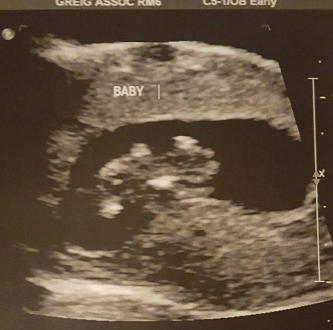

This was our second scan, so excited to see it resembling a little human now!!! Does anyone else notice the blank space to the left of the baby? My curious mind wonders if that could be another one? Dr only did vaginal. Thoughts?